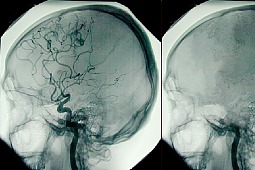

- Do śmierci mózgu może dojść w wyniku pierwotnego uszkodzenia mózgu albo kilka minut po zatrzymaniu krążenia, wtedy kiedy krew już przez mózg przestaje krążyć i obumiera on bardzo szybko, w okresie kilku minut - wyjaśnia prof. Bohatyrewicz z PUM. - To w zasadzie w kręgach medycznych nie stanowi już większego problemu i nasze polskie społeczeństwo też już to przyjęło do wiadomości w znakomitej większości.